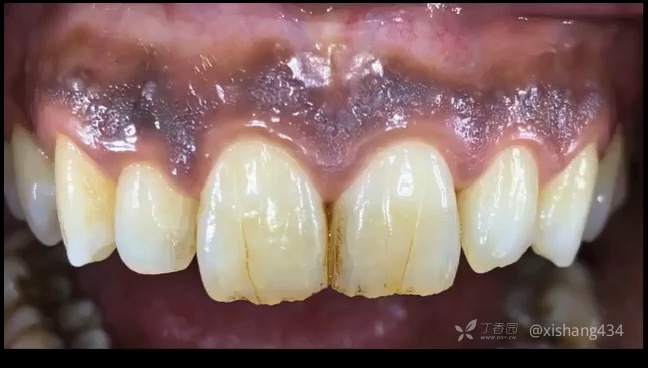

临床上有一些患者牙龈黑色素沉着,传统的方法脱色有手术刀,金钢砂车针磨除,操作均不方便。采用激光脱色,操作简便,效果也不错。